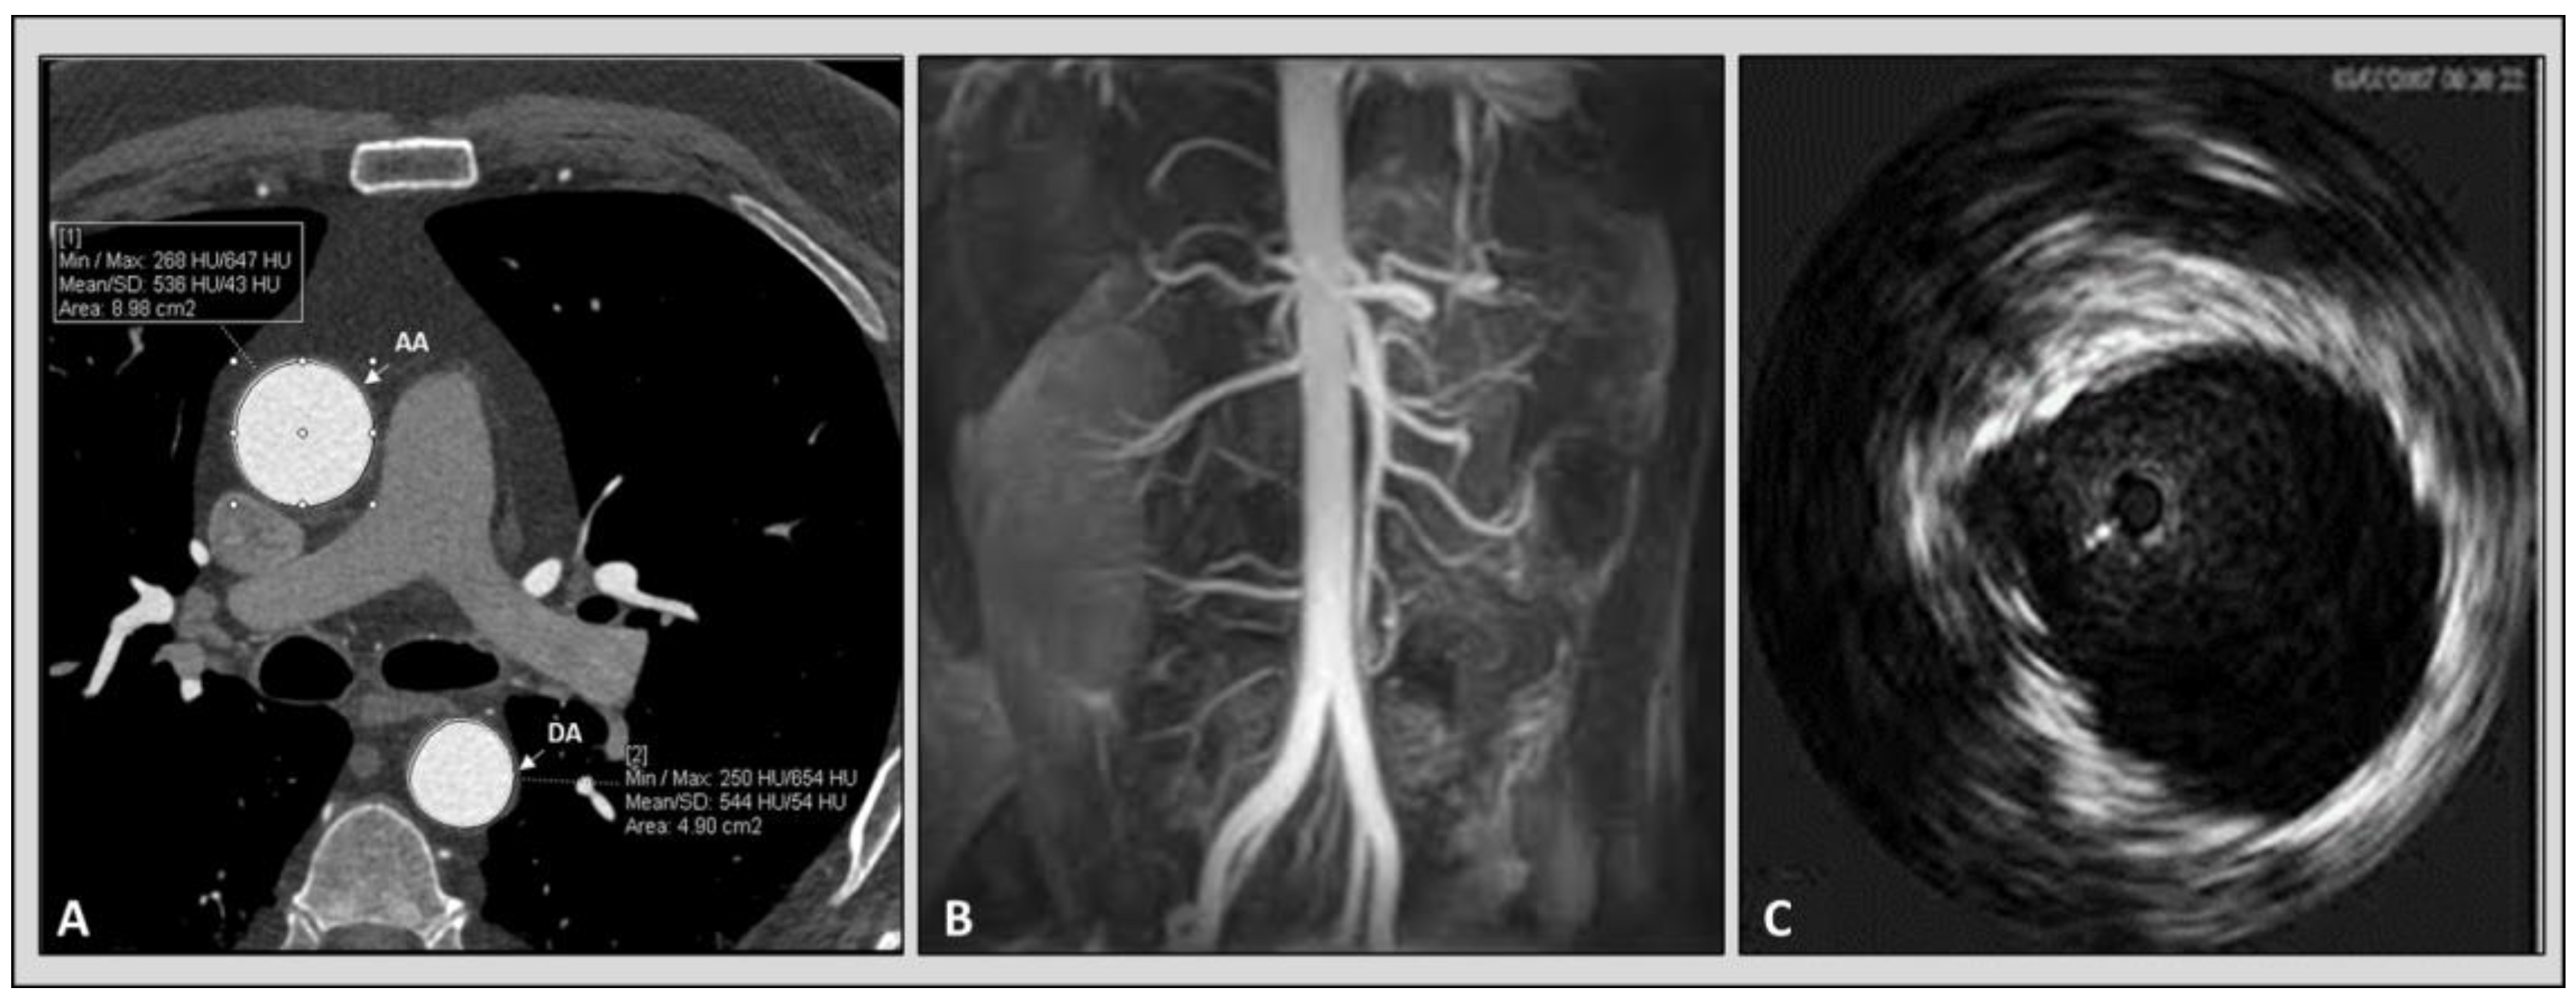

Figure 3. Imaging modalities available for the evaluation of aortic elastic properties. Panel (A): computed tomography angiography. Panel (B): magnetic resonance angiography. Panel (C): intravascular ultrasound imaging of aorta. Copyright: authors.